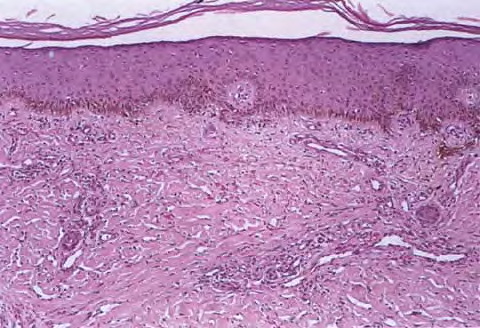

The histopathology of KS is dependent on the stage of KS development. Early patch-like lesions exhibit rather discrete histopathologic changes, consisting mainly of an increase in the number of dermal vessels, outlined by slightly irregular endothelial cells (Fig. 128-5). These vessels, located mainly in the superficial dermis are parallel to the skin surface, are frequently slightly irregular, and may form bizarre slits and clefts. In the surrounding skin focal hemosiderin, deposits and extravasated erythrocytes can be found as well as a moderate inflammatory infiltrate. Important differential diagnoses of this stage include lymphangioma and granulation tissue.